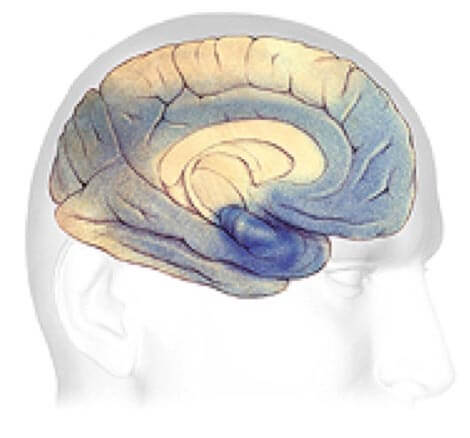

Alzheimer's disease leads to nerve cell death and tissue loss throughout the brain. Over time, the brain shrinks dramatically, affecting nearly all its functions.

These images show:

How the two brains compare.

Progression Through the Brain

Plaques and tangles (shown in the blue-shaded areas) tend to spread through the cortex in a predictable pattern as Alzheimer's disease progresses. The rate of progression varies greatly. On average, a person with Alzheimer's lives four to eight years after diagnosis, but can live as long as 20 years, depending on other factors. The course of the disease depends in part on age at diagnosis and whether a person has other health conditions.

Severe Alzheimer's - may last from 1 - 5 years.

Severe Alzheimer's Disease

In advanced Alzheimer's disease, most of the cortex is seriously damaged. The brain shrinks dramatically due to widespread cell death. Individuals lose their ability to communicate, to recognize family and loved ones and to care for themselves.